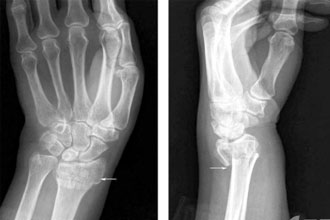

X线能清楚地拍出骨性结构(下图中白色轮廓清晰部分)但却不能清晰地分辨出软组织结构(边缘白色模糊部分)。因此,在常规摄片排除骨折表现后,患者通常会把受伤局部的肿胀、疼痛及运动障碍等不适,统称为“伤筋”,医学上则称为“软组织损伤”。

图1 手部X线片(白色部位为骨骼,边缘白色模糊部分为软组织)

图片来源:X线读片指南——王书轩、范国光主编